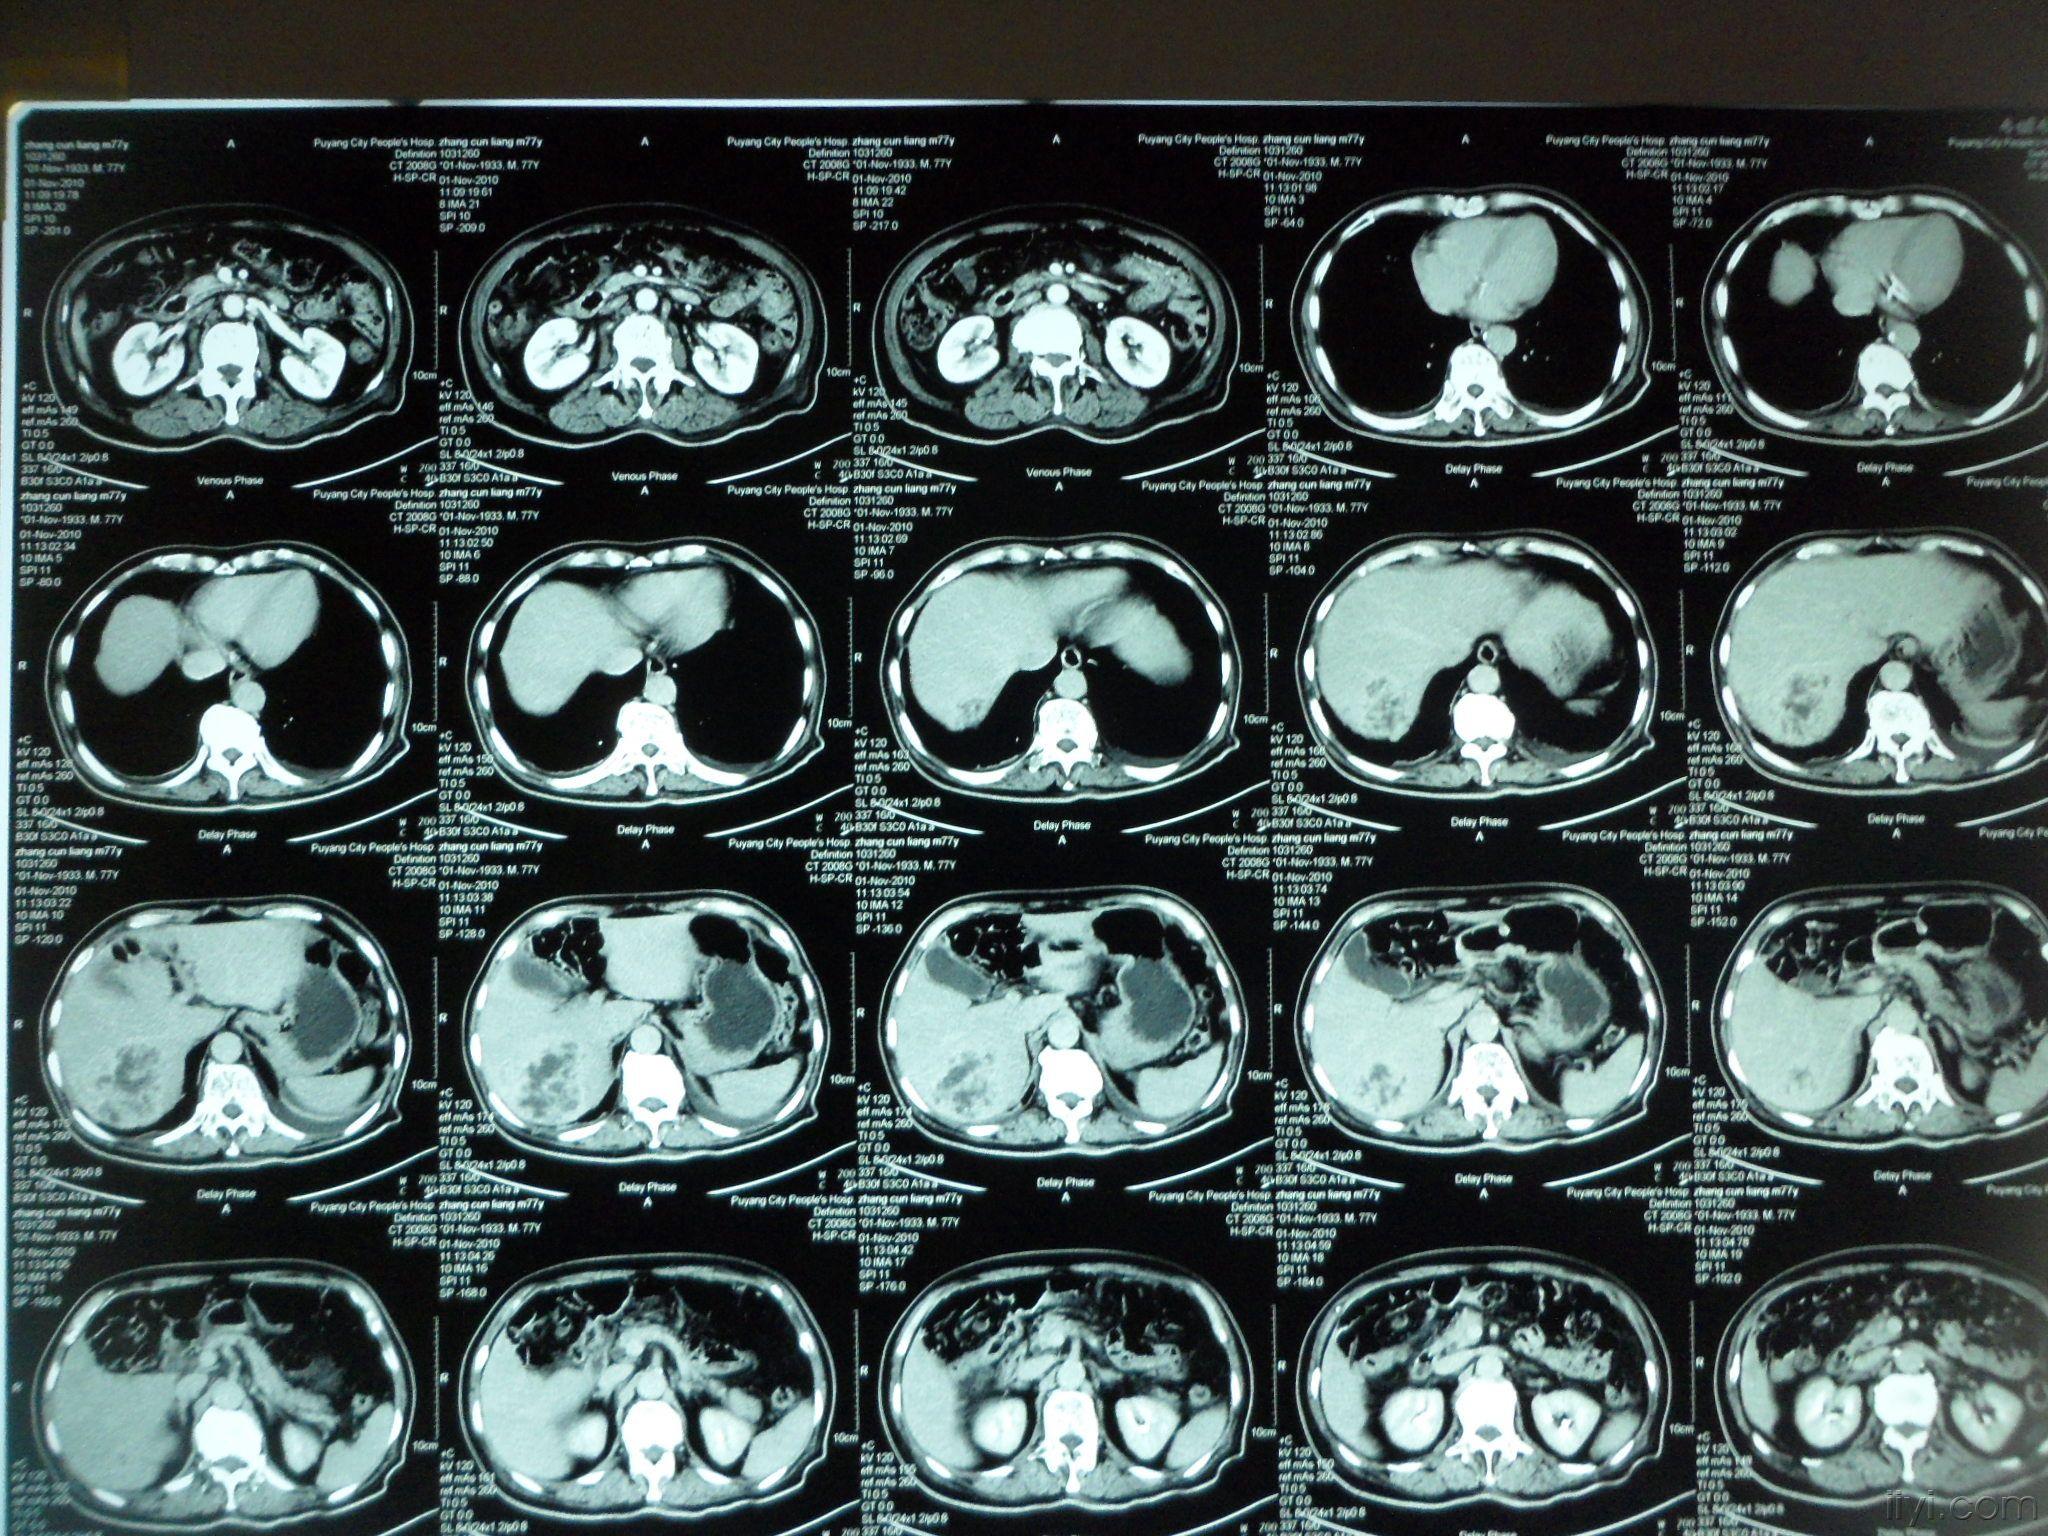

楼主hizhouyue2010-11-19 13:53:55 大家一起看看这个ct片子,说说你

图片尺寸2048x1536